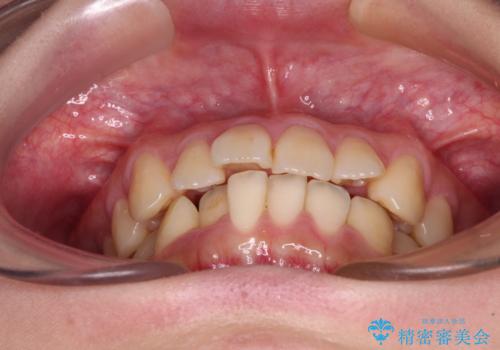

- 前歯の捻れを気にして来院された患者様です。

上顎前歯が捻れて前方に飛び出しており、下顎前歯もそれに沿うようにデコボコとなっていました。

IPR(歯と歯の間を削る処置)によりスペースを獲得して下顎前歯のデコボコを改善し、上顎前歯は下顎前歯と接する位置にまで引っ込めるように設定し、インビザラインにて矯正治療を行うこととしました。

しっかりと装着時間を守ってくださったので、予定通り1年強で治療を終えることができました。